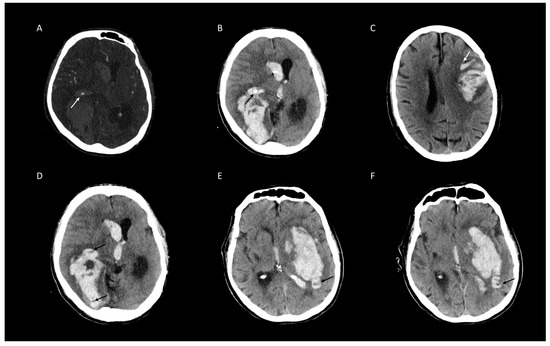

2.3. Image Analysis